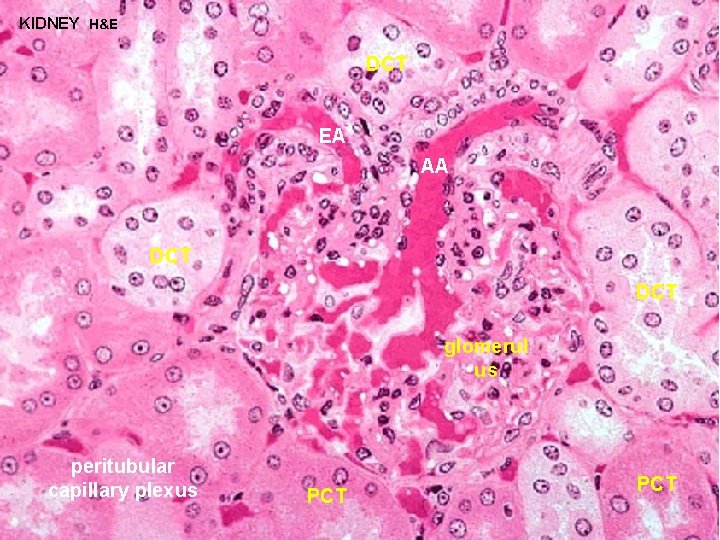

KIDNEY H&E PCT DCT glomerul us DCT PCT PCT

KIDNEY H&E DCT EA AA DCT glomerul us peritubular capillary plexus PCT

URINARY SYSTEM JUXTAGLOMERULAR MACULA DENSA + JUXTAGLOMERULAR (JG) APPARATUS CELLS REGULATE BLOOD FLOW THROUGH GLOMERULUS MACULA DENSA - cells located in the DCT in close contact with the glomerulus and the afferent and efferent arterioles JG CELLS - specialized smooth muscle cells in the wall of the afferent arteriole which contain and secrete RENIN to regulate blood flow through the glomerulus ANGIOTENSINGO GEN (PLASMA PROTEIN) RENIN ANGIOTENSIN II ALDOSTERONE SECRETION VASOCONSTR

URINARY SYSTEM JUXTAGLOMERULAR MACULA DENSA + JUXTAGLOMERULAR (JG) APPARATUS CELLS REGULATE BLOOD FLOW THROUGH GLOMERULUS BARORECEPTOR THEORY - assumes JG cells function as stretch receptors (high blood pressure would inhibit release of renin) MACULA DENSA THEORY - assumes the secretion of renin is regulated by the composition of the fluid in the DCT / afferent arteriole (low sodium would increase the release of renin) ANGIOTENSINGO GEN (PLASMA PROTEIN) RENIN ANGIOTENSIN II ALDOSTERONE SECRETION VASOCONSTR